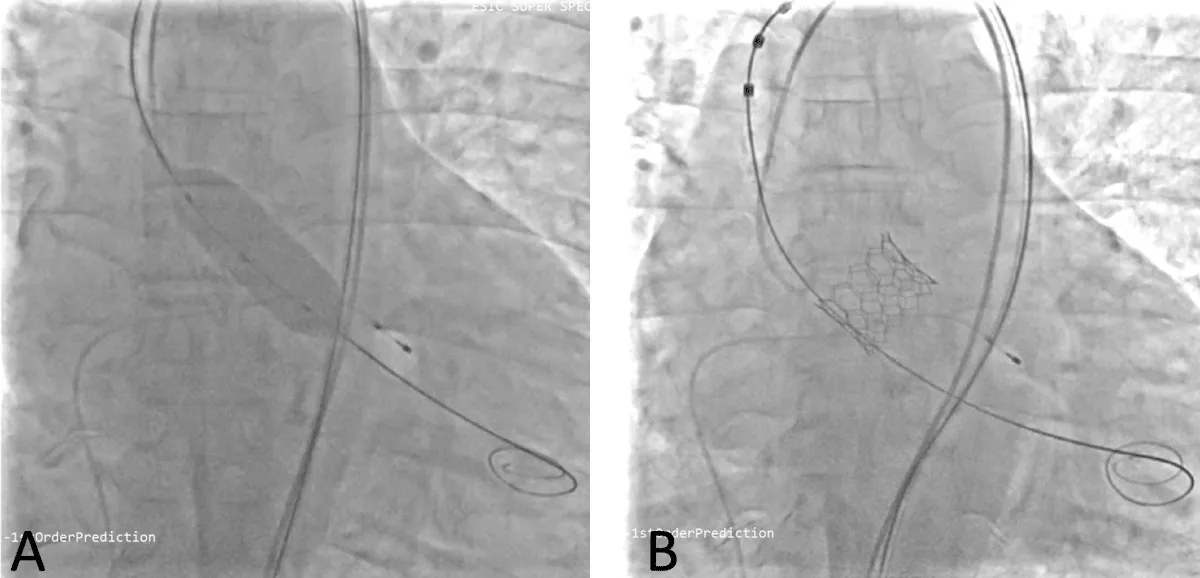

After obtaining consent, access was obtained through the right femoral vein and artery. Under 4D Transesophageal Echocardiography (4D TEE) guidance, the first transseptal puncture was performed with a broken Brough needle, and the LA wire was inserted through femoral venous access (Figure 1). Right femoral artery access was used for retrograde crossing of the aortic valve (AV) (Figure 2), and a Teflon wire was placed in the left ventricle. The aortic valve (AV) was dilated with a 14 mm ATLAS GOLD (BARD) balloon (Figure 3, Video 1).

Figure 1: A,B: 4Dimensional multiplanar transoesophageal echocardiography. A. 4D image with Left atrial wire, B. Severe mitral stenosis with mitral area of 0.5 cm2, 1C &1D. Showing multiplane of mitral valve.

Following a single dilatation, the AV gradient decreased from 82 mm Hg to 30 mm Hg without aortic regurgitation (AR). Subsequently, the mitral valve (MV) was dilated with a 26 mm Inoue balloon (Figures 4,5) (Video 2). After a single dilatation, the MV gradient was reduced from 35/21 mm Hg to 12/5 mm Hg, and the MV area increased from 0.5 cm2 to 1.6 cm2 (Figure 6)